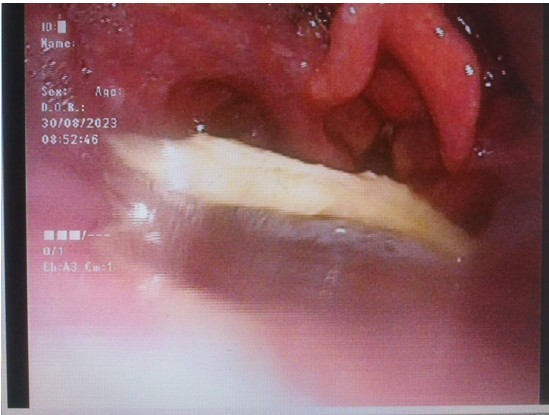

圖片一:電子鼻咽喉鏡顯示方形異物卡在喉咽部

面對(duì)困難,庾江東主任請(qǐng)來(lái)耳鼻咽喉頭頸外科主任醫(yī)師、副主任唐先龍,呼吸與危重癥醫(yī)學(xué)科副主任醫(yī)師羅勇飛,技師黃君。大家仔細(xì)研究卡住的鴿子骨頭,獻(xiàn)計(jì)獻(xiàn)策,不斷調(diào)整吸取設(shè)備,改善吸取方案,轉(zhuǎn)移診療室,在4位專家的合力支持配合下,經(jīng)過(guò)近2個(gè)小時(shí)的努力,終于在電子鼻咽喉鏡引導(dǎo)下,將一塊6x5㎝的鴿子骨頭從口腔取出來(lái)了!病人和家人都萬(wàn)分感謝!